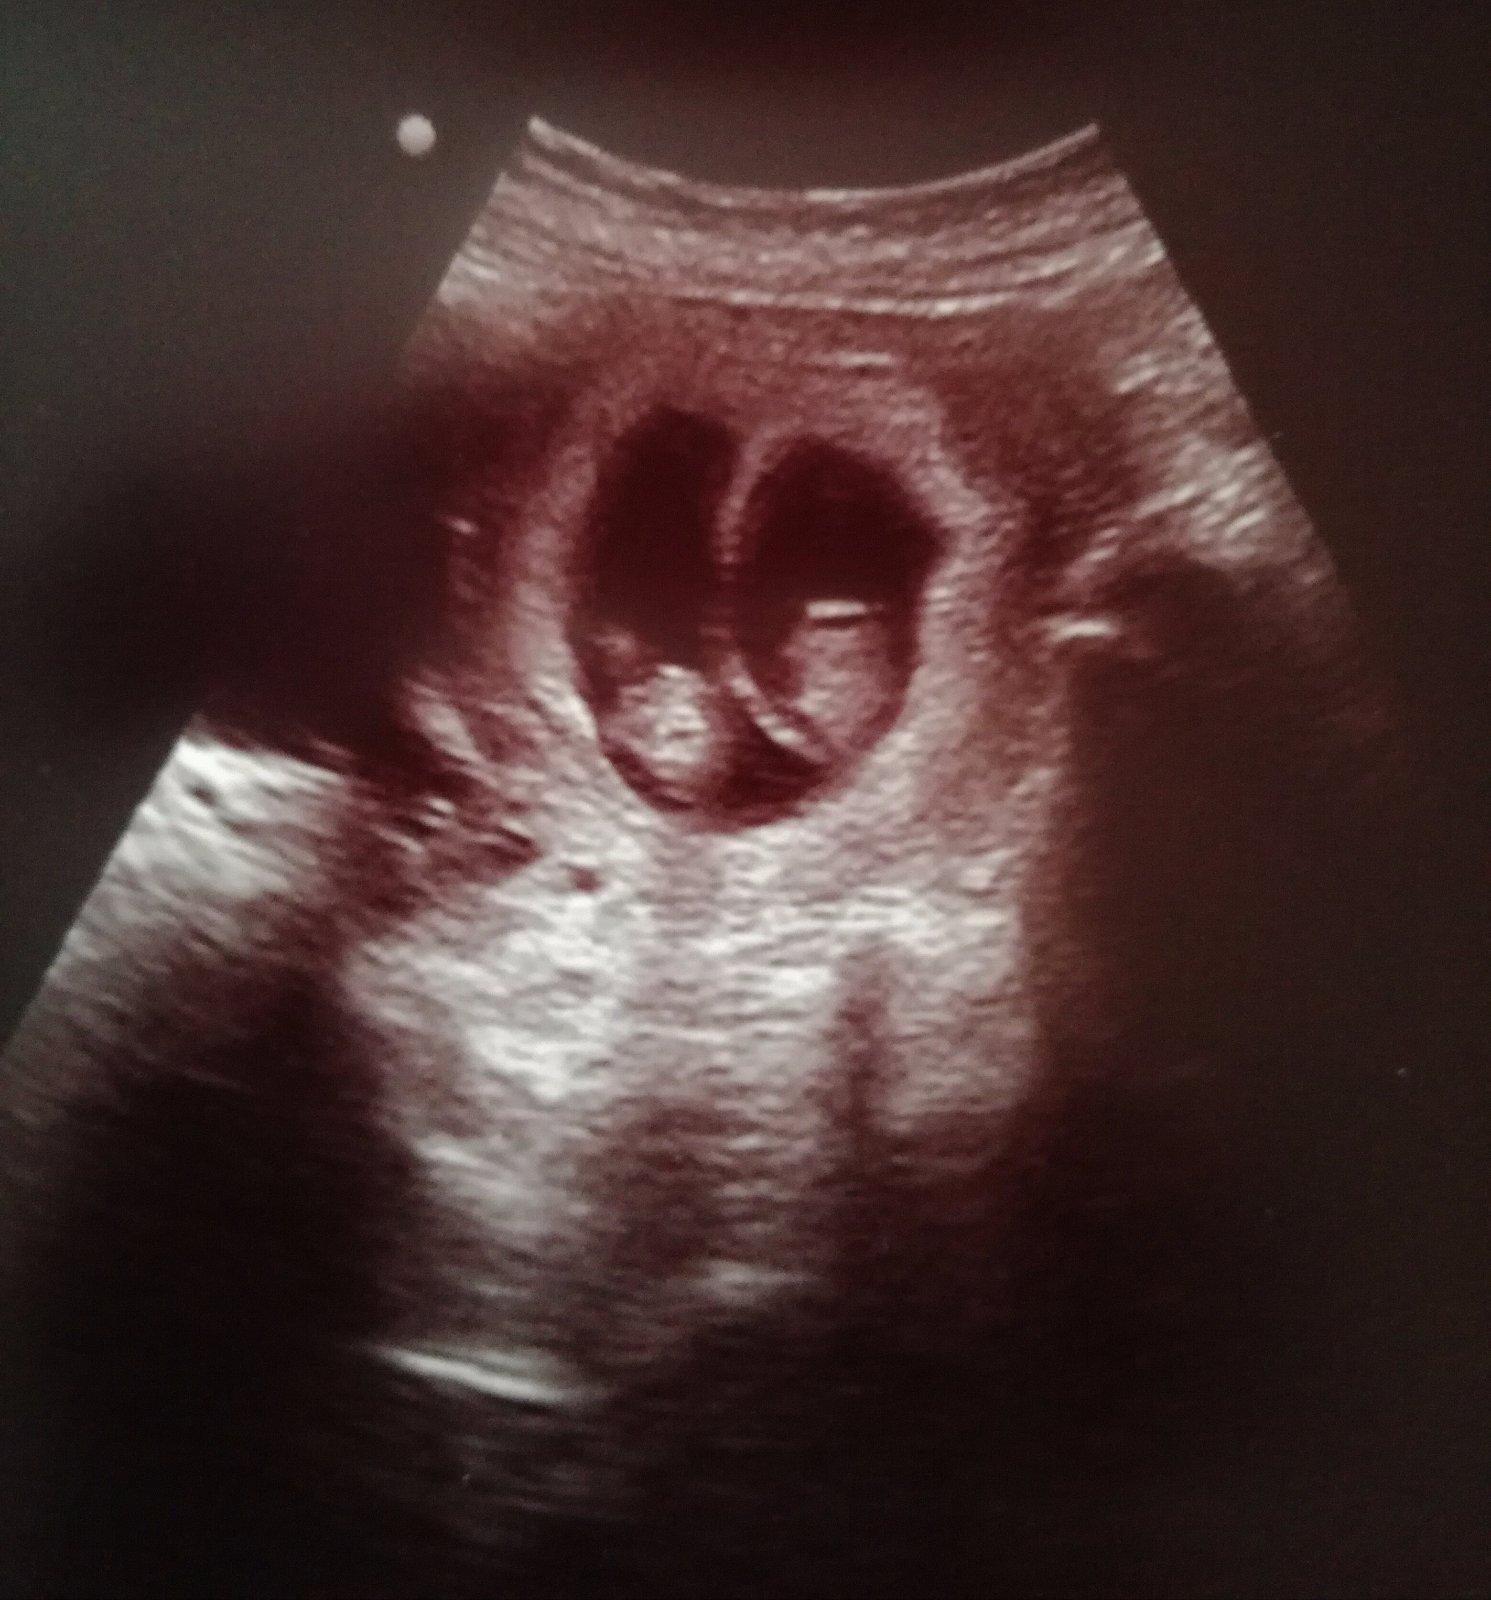

@janulka232 Ahoj tak dnešné sono dopadlo nad všetky moje očakávania. Z jednej fazuľky sú dve 😅. Podľa sona sme 8+4 (20mm) a 8+2 (18mm). Zatiaľ je všetko v poriadku. Prvý šok, keďže sme to nečakali vystriedala radosť. Bude to asi ťažké, no verím, že všetko dopadne dobre a bude tak ako má byť.